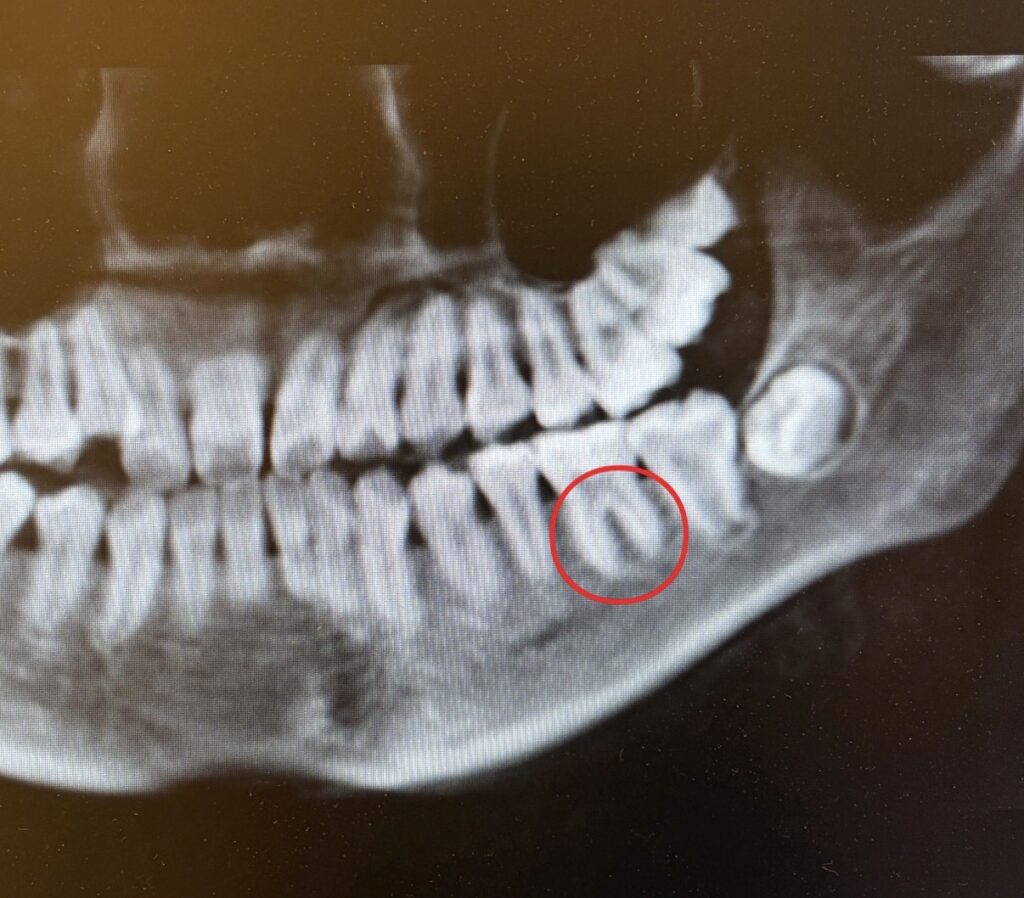

治療前

治療後

歯根吸収とは、矯正治療中に歯の根の一部がごくわずかに短くなる現象です。

歯は骨の中に埋まっていますが、矯正で動かす際には「骨のリモデリング」が起こり、その過程で歯の根の表面にも軽度の変化が生じます。

◆ ① 治療前の精密検査(CT/パノラマ)

根の形・長さ・骨の状態を事前に把握します。

これが“予測とリスク評価の基礎”になります。